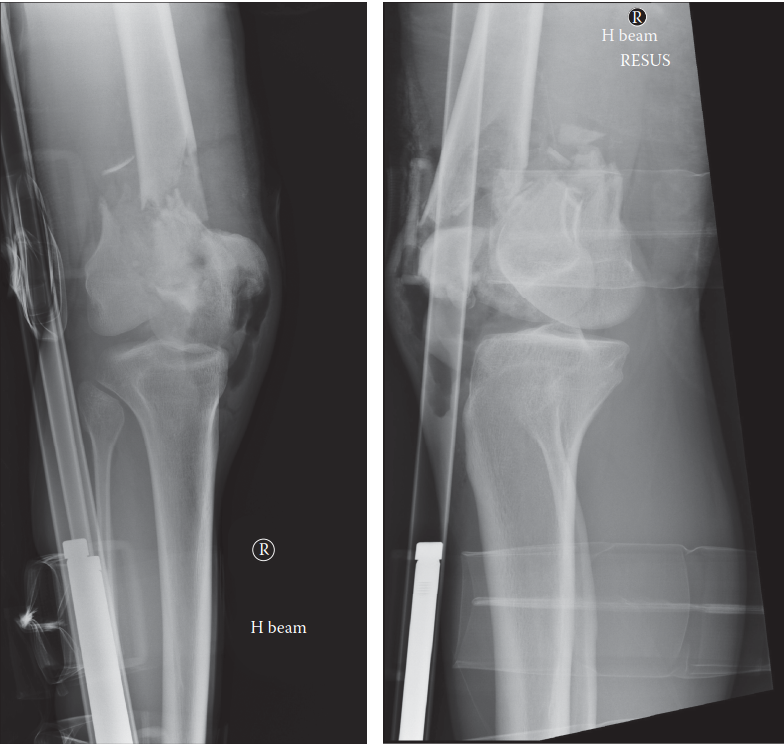

Can you describe the radiographs? This is a highly comminuted distal femoral fracture. There is gas in the so…